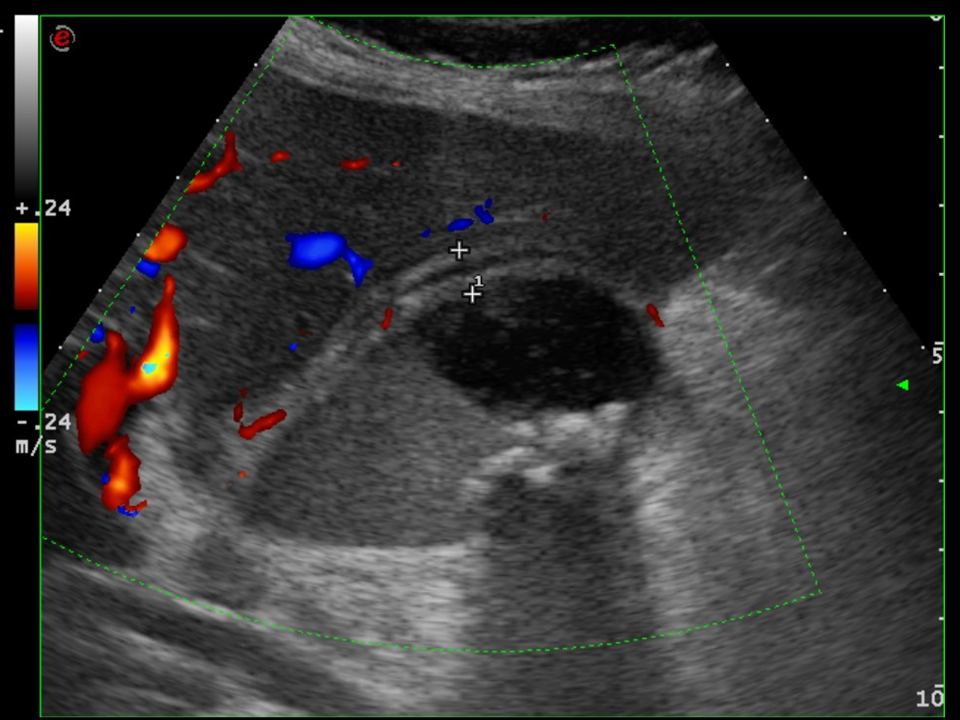

• A knife falling from a kitchen table stuck into the right thigh of an 18 year old young man. Increased femoral circumference and pulsating mass were seen. In the upper image with femoral Duplex sonography pseudoaneurysm of the femoral artery is detected

In the middle with a CT angiography the pseudoaneurysm shows contrast enhancement.

In the lower image 3D reconstruction of the CTA

11. A knife falling from a kitchen table stuck into the right thigh of an 18 year old young man. Increased femoral circumference and pulsating mass are seen. In the upper image with femoral Duplex sonography pseudoaneurysm of the femoral artery is detected In the middle with a CT angiography the pseudoaneurysm shows contrast enhancement. In the lower image 3D reconstruction of the CTA